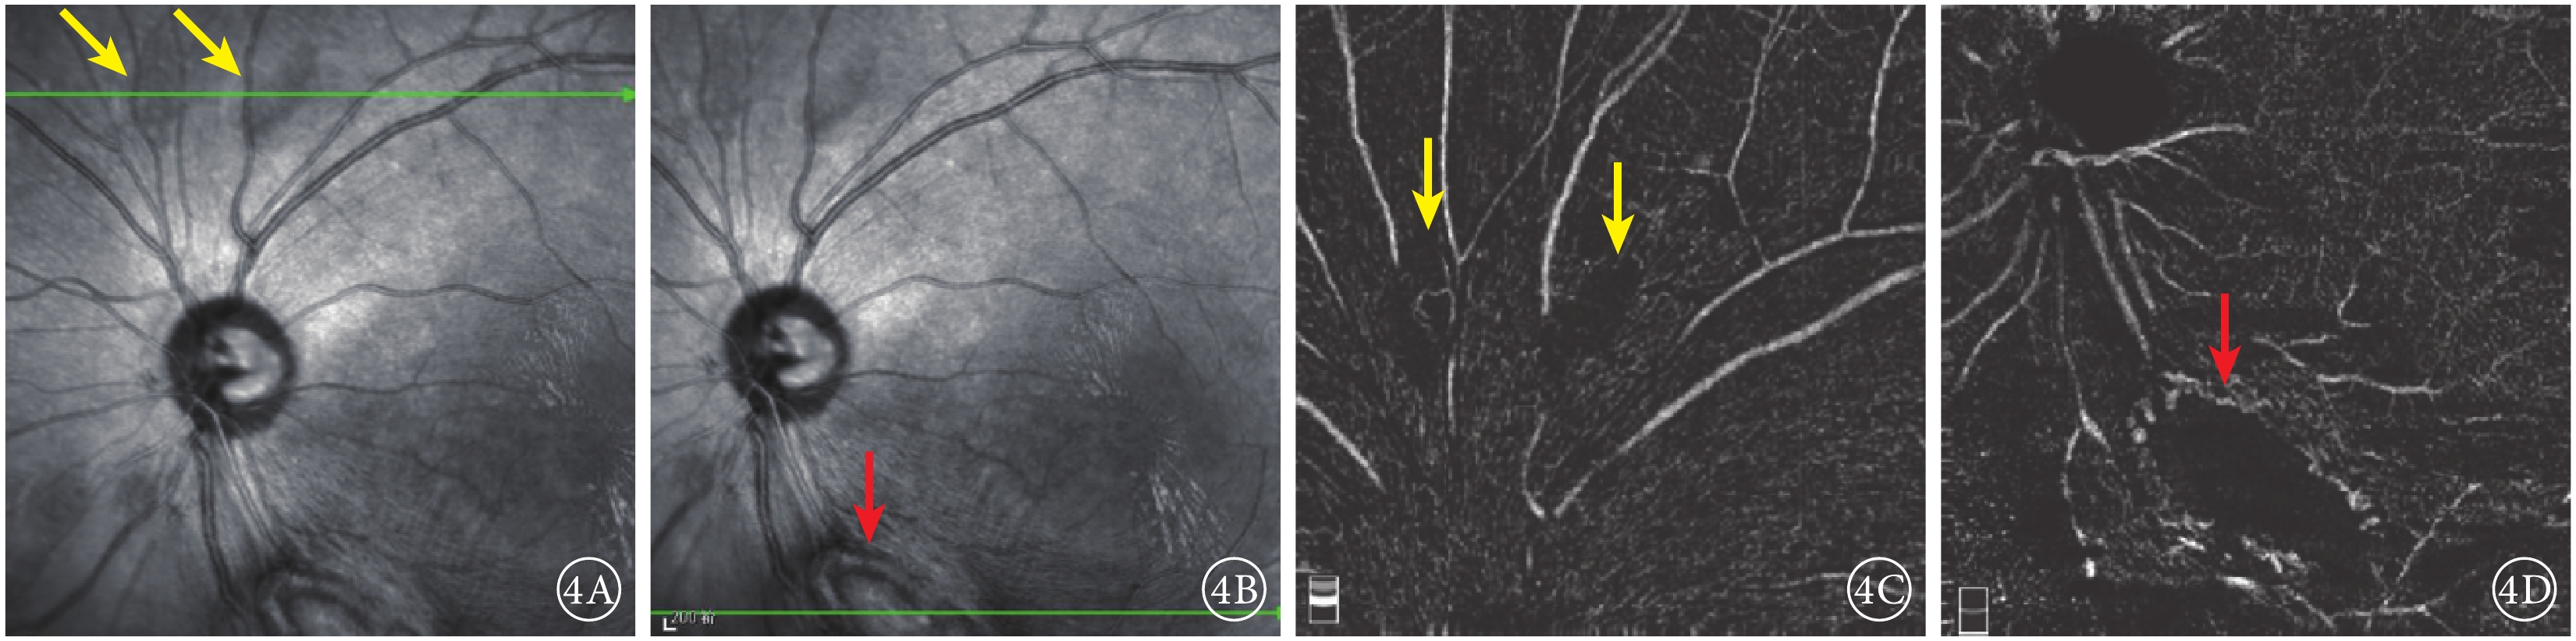

圖4

患者左眼IR及OCTA像。 4A.IR像,視盤上方可見兩處類橢圓形病灶(黃箭);4B.IR像,視盤下方大病灶隆起,結構紊亂(紅箭);4C.OCTA像,與圖4A對應病灶處未見明顯異常;4D.OCTA像,與圖4B對應病灶處周邊部分可見血流信號(紅箭)

圖4

患者左眼IR及OCTA像。 4A.IR像,視盤上方可見兩處類橢圓形病灶(黃箭);4B.IR像,視盤下方大病灶隆起,結構紊亂(紅箭);4C.OCTA像,與圖4A對應病灶處未見明顯異常;4D.OCTA像,與圖4B對應病灶處周邊部分可見血流信號(紅箭)

紅外眼底成像(IR)檢查,左眼視盤下方隆起病灶,結構紊亂,視盤上方可見兩處類橢圓形病灶(圖4A,4B)。光相干斷層掃描(OCT)血管成像(OCTA)檢查,左眼視盤下方病灶周邊部分可見血流,其余小病灶未見明顯異常(圖4,4D)。結合病史及輔助檢查,診斷為結節性硬化并發視網膜星形細胞錯構瘤。OCT檢查,左眼視盤下方視網膜光帶呈圓頂狀隆起,光帶增寬且反射增強,病灶內呈蟲蝕狀,各層結構不清,周圍視網膜層間水腫伴神經上皮脫離,其余各病灶對應區域OCT斷面上視網膜內層光帶增厚隆起,反射增強(圖5)。

圖4

患者左眼IR及OCTA像。 4A.IR像,視盤上方可見兩處類橢圓形病灶(黃箭);4B.IR像,視盤下方大病灶隆起,結構紊亂(紅箭);4C.OCTA像,與圖4A對應病灶處未見明顯異常;4D.OCTA像,與圖4B對應病灶處周邊部分可見血流信號(紅箭)

圖4

患者左眼IR及OCTA像。 4A.IR像,視盤上方可見兩處類橢圓形病灶(黃箭);4B.IR像,視盤下方大病灶隆起,結構紊亂(紅箭);4C.OCTA像,與圖4A對應病灶處未見明顯異常;4D.OCTA像,與圖4B對應病灶處周邊部分可見血流信號(紅箭)

紅外眼底成像(IR)檢查,左眼視盤下方隆起病灶,結構紊亂,視盤上方可見兩處類橢圓形病灶(圖4A,4B)。光相干斷層掃描(OCT)血管成像(OCTA)檢查,左眼視盤下方病灶周邊部分可見血流,其余小病灶未見明顯異常(圖4,4D)。結合病史及輔助檢查,診斷為結節性硬化并發視網膜星形細胞錯構瘤。OCT檢查,左眼視盤下方視網膜光帶呈圓頂狀隆起,光帶增寬且反射增強,病灶內呈蟲蝕狀,各層結構不清,周圍視網膜層間水腫伴神經上皮脫離,其余各病灶對應區域OCT斷面上視網膜內層光帶增厚隆起,反射增強(圖5)。

討論 結節性硬化病是一種少見的以皮膚、腦、腎、眼等多系統錯構瘤為特征的綜合征[1]。本例患者存在皮膚纖維斑塊,面部纖維血管瘤、指甲纖維瘤、腎臟錯構瘤、視網膜錯構瘤等多項主要特征。說明其結節性硬化病診斷成立[1]。視網膜星狀細胞錯構瘤是結節性硬化病的常見眼部病變,多表現為多灶性和雙側性[2]。根據形態學分型,視網膜星狀細胞錯構瘤可分為小的半透明平滑病灶(Ⅰ型)、大的鈣化結節病灶(Ⅱ型)和兩種病灶混合存在(Ⅲ型)3種類型[3]。本例患者Ⅰ型、Ⅲ型病灶并存。左眼視盤下方的大病灶為Ⅲ型病灶,病灶周圍并發滲出性視網膜脫離及視網膜層間水腫,這可能與病灶處存在牽拉、血視網膜屏障遭到破壞有關;其余各病灶均為Ⅰ型病灶。

我們對本例患者行多模式影像檢查。OCT可清晰顯示病灶細節及所在的視網膜層次。OCTA檢查提示瘤體內含血管成分,故FFA顯示病灶晚期熒光素滲漏;由于各病灶血管含量及通透性不一致,故熒光素滲漏情況存在差異。左眼視盤下方病灶較厚,對視網膜色素上皮形成遮擋,因此在FAF上呈現弱AF,其余各病灶均未見明顯異常AF改變。超廣角眼底彩色照相成像范圍廣,眼底各個病灶均可觀察到。IR可較清晰觀察到病灶,并與OCT實時對應,輔助OCT定位掃描。我們分析超廣角眼底彩色照相、IR及OCT之所以能夠較明顯地觀察到病灶的原因是,均為單一波長激光,反射后聚焦在同一點上,組織對其吸收較少,故可得到更清晰的圖像[3]。三者結合可以更全面細致地觀察視網膜星狀細胞錯構瘤各病灶,既利于臨床高效診斷及鑒別診斷,又便于對病灶進行長期觀察。